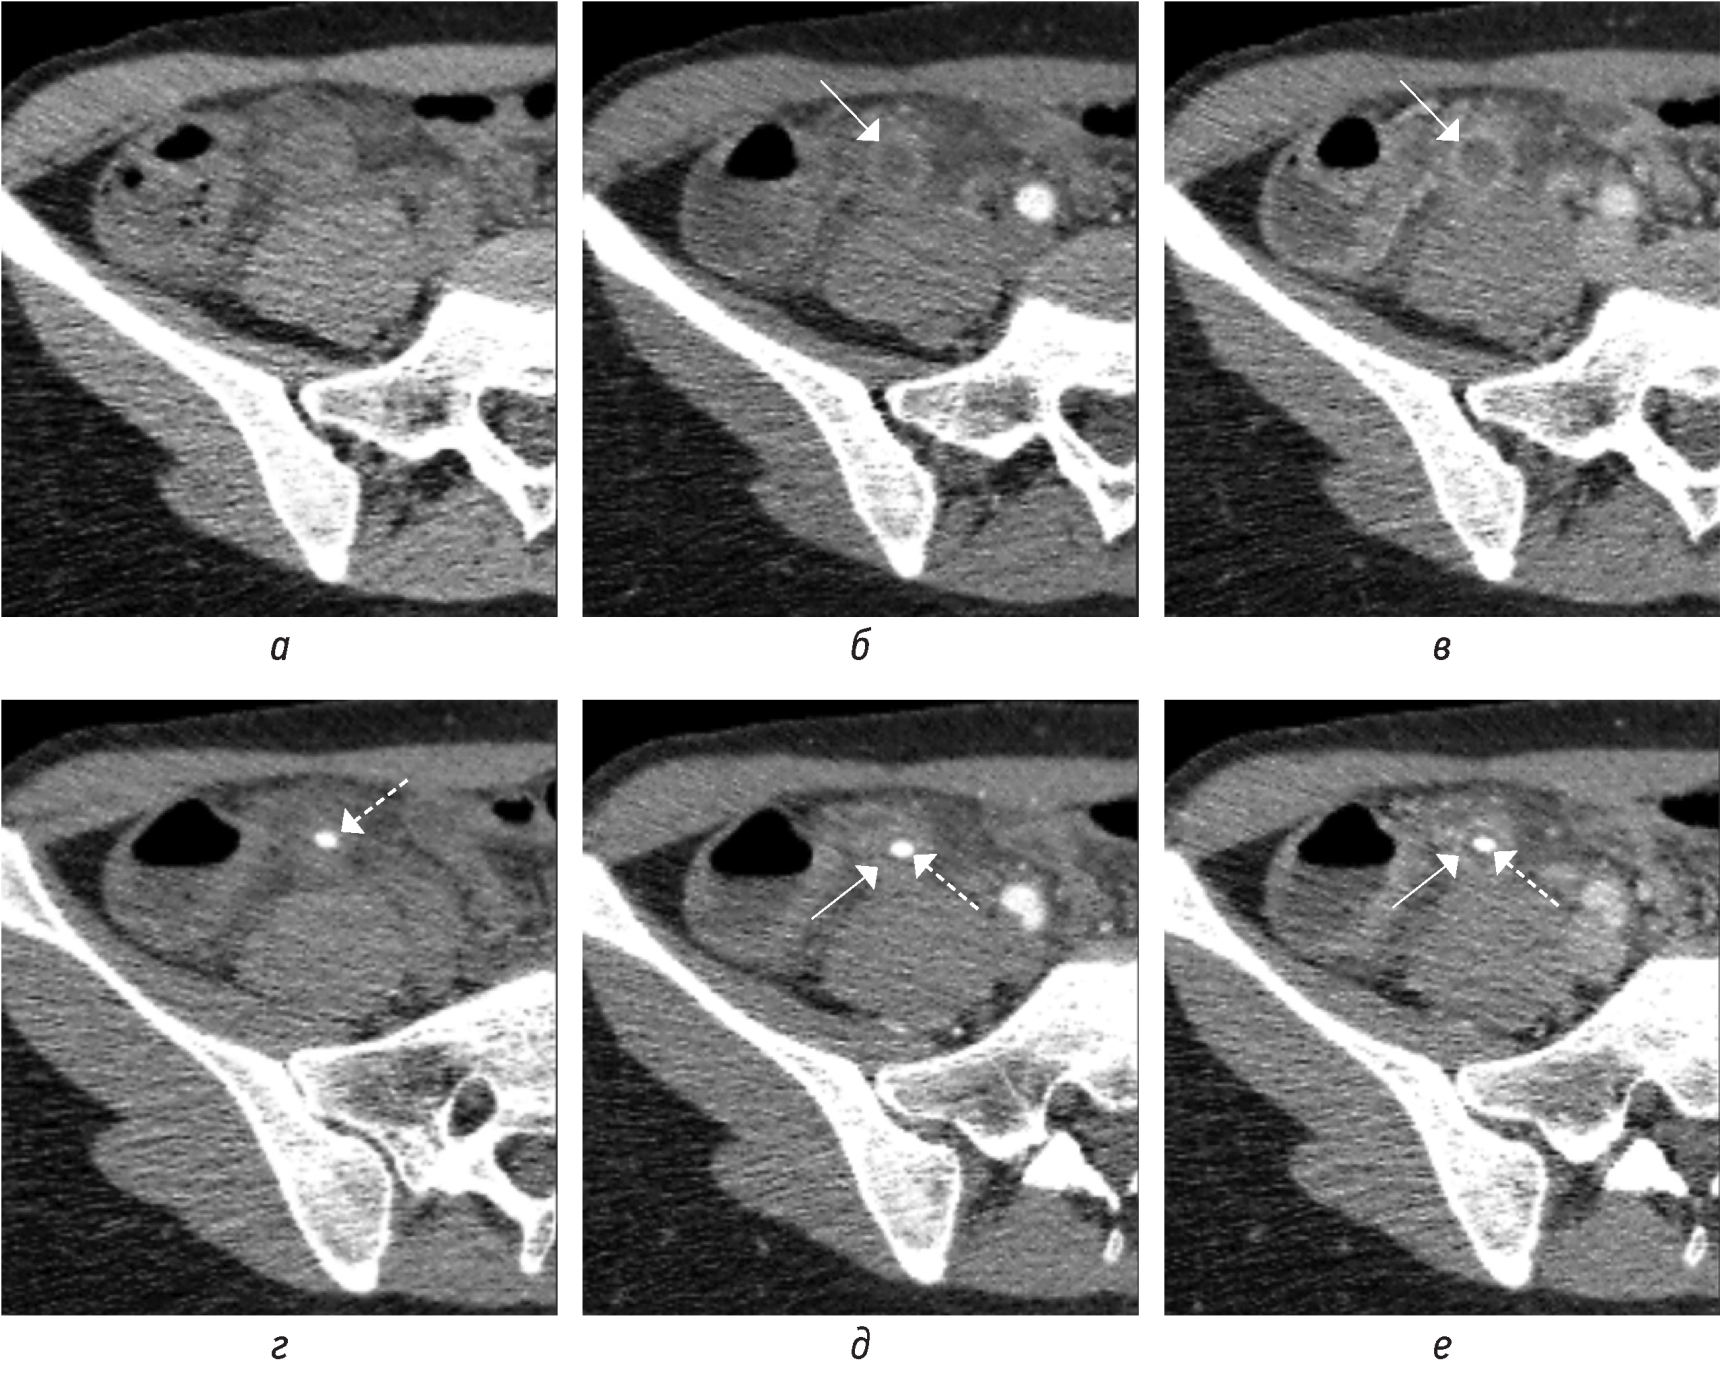

В наши дни наиболее часто используемым протоколом является нативная КТ живота и таза с последующим внутривенным введением контрастного вещества и (иногда) пероральным контрастированием. Рекомендуется использовать однофазное, а не многофазное сканирование, чтобы избежать любой дополнительной дозы [21]. Наиболее информативной для оценки является портовенозная фаза [3] (рис. 1, а–е).

Рис. 1. На КТ-изображениях в аксиальной плоскости в нативную (а, г), артериальную (б, д), портовенозную (в, е) фазы на двух уровнях демонстрируется накопление контрастного вещества стенками аппендикулярного отростка (стрелка) в разные постконтрастные фазы в сравнении с нативной. В просвете аппендикса на фоне жидкостного содержимого визуализируется феколит (пунктирная стрелка)

Fig. 1. CT images in the axial plane in the native phase (а, г), arterial phase (б, д), portovenous phase (в, е) at two levels demonstrate the accumulation of contrast agent by the walls of the appendicular process (arrow) in different post-contrast phases in comparison with the native. In the lumen of the appendix, fecal matter is visualized against the background of liquid contents (dotted arrow)